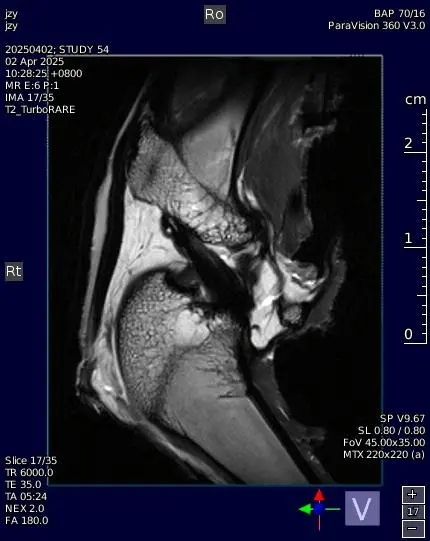

磁共振成像(MRI)凭借其卓越的软组织对比度,能够精细显示脏器解剖结构,支持多参数成像,为神经科学和心血管研究提供有力支持。